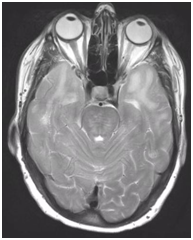

During follow-up in stroke clinic, her imaging was reviewed. MR imaging demonstrated large confluent areas of hyperintense T2 and FLAIR signal abnormality throughout the periventricular and deep white matter with extension into the subcortical white matter (Figure 1) (Figure 2). T1w images demonstrated low signal, corresponding to the T2/FLAIR abnormality on T2w images. This white matter abnormality is known as leukoaraiosis. The hyperintense T2/FLAIR signal abnormality also involved the anterior temporal lobes (Figure 3) (Figure 4) and external capsules (Figure 5) (Figure 6). This feature on MRI is uncharacteristic of other white matter diseases, notably the sporadic subcortical atherosclerotic encephalopathy. In our patient, the corpus callosum was spared. The lacunar infarcts were small vessel infarcts, typically seen in the deep white matter, basal ganglia, thalami, and the pons. On diffusion images, there was a small area of diffusion restriction in the left corona radiata that was consistent with an acute infarct (Figure 7) (Figure 8). Subsequently, there was an area of encephalomalacia on follow-up MRI at the location of the previous acute infarct. This abnormality correlated with the right-sided weakness seen prior to the index patient’s admission.

Figure 3 T2 axial image demonstrates hyperintense white matter signal involving the anterior temporal lobes on both sides.

Figure 4 FLAIR axial image demonstrates hyperintense signal in white matter in anterior temporal lobes, on both sides which is more conspicuously seen compared to T2 signal seen on Figure 3.